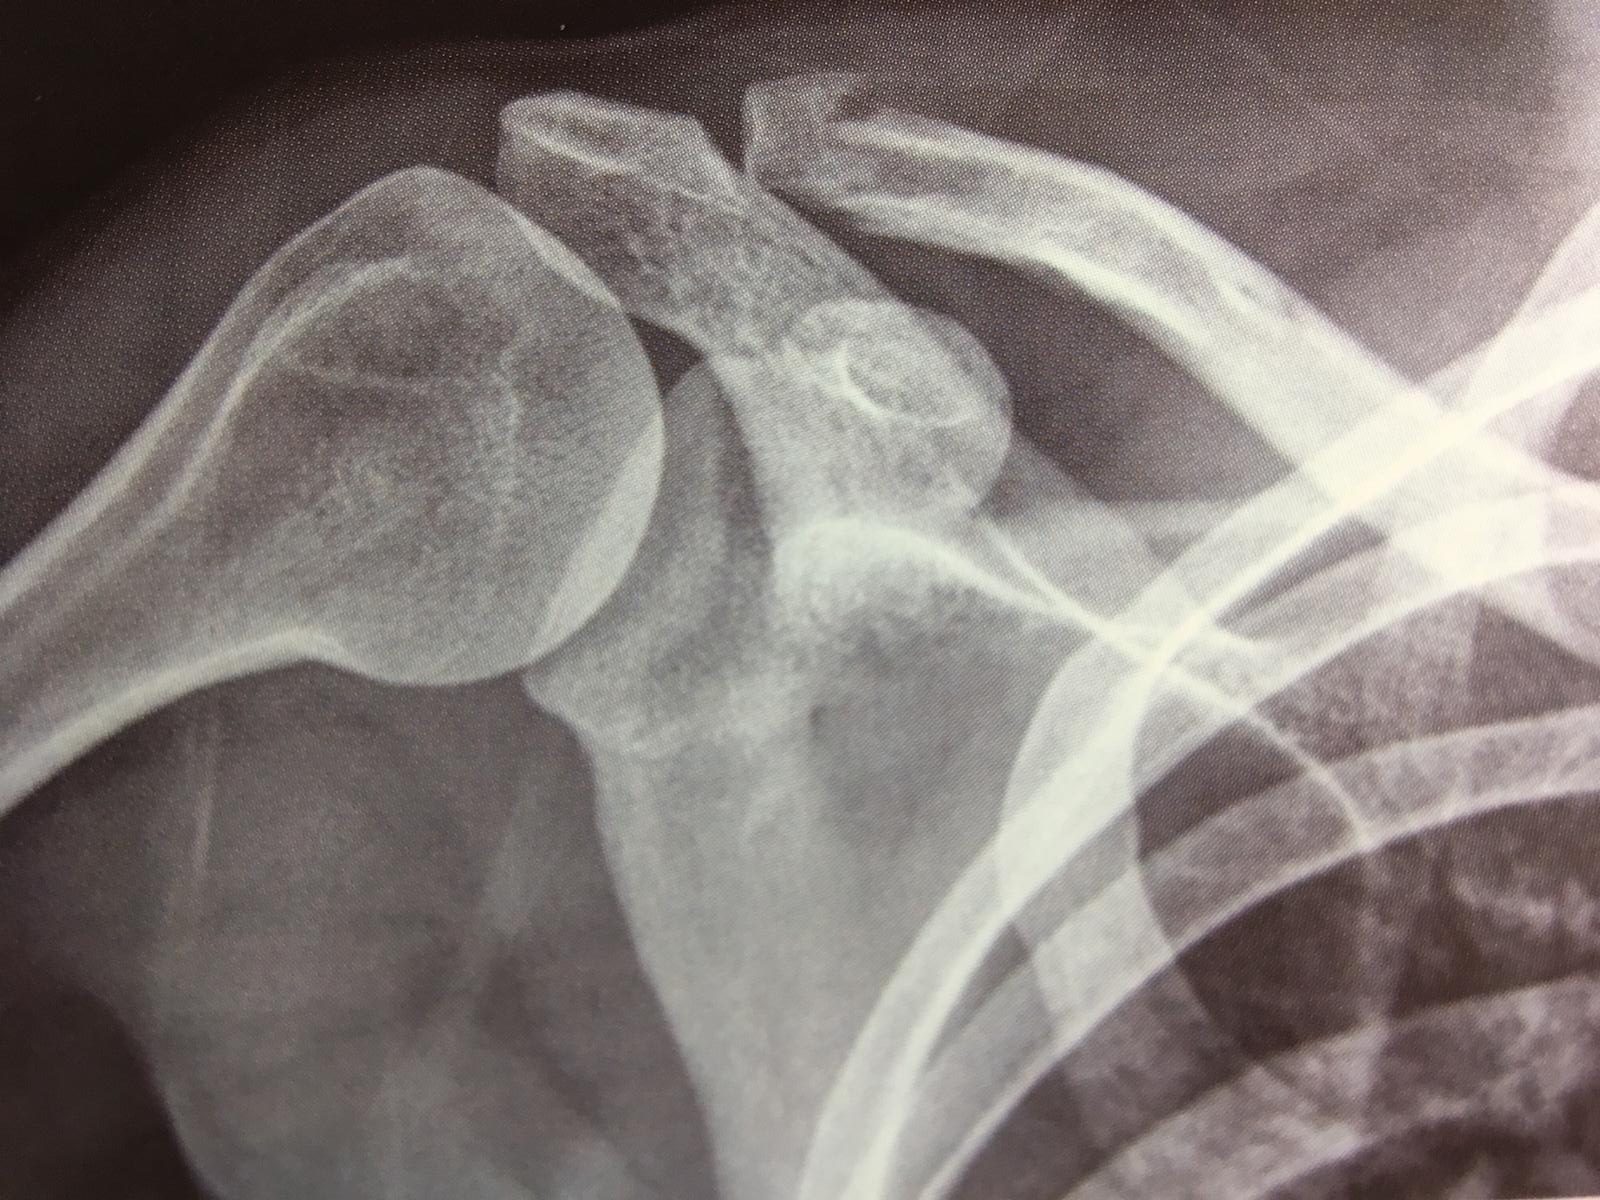

Ed unita alla clavicola grazie a dei fasci di legamenti. Lussazione acromion claveare di quarto grado.

Artrite acromion claveare (per lo più nelle forme dell'estremo distale). L'artrosi acromion claveare è una delle cause più comuni di dolore alla spalla. Dopo caduta ho riportato una distorsione acromion claveare spalla dx, lieve (come da rx di pronto soccorso), frattura al corpo della scapola e frattura scomposta della 3° e 4° costola. Lussazione di ii/iii° legamenti acromion claveare (+ 3 costole fratturate). Inizialmente fino ai 17 anni le superfici sono rivestite da cartilagine jalina che viene poi. Frattura dell'estremo distale della clavicola destra è la tipica causa di dolore alla clavicola. Acromion claveare, coraco per avere una conferma dell'ipotesi di diagnosi e per escludere la presenza di possibili fratture. I sintomi e 3 scrutiny. Scopriamo cos'è la diastasi dell'articolazione acromion claveare e come riconoscerla, infine di solito si verifica una lesione dei tessuti molli o dei legamenti, ma può avvenire anche una frattura. Ricerca e cura in riabilitazione. Acromion claveare è una diartrosi costituita dall'1/3 laterale della clavicola e dal margine mediale dell'acromion. ✓ tutte le informazioni che cerchi in un unico sito di fiducia. Acromion claveare | scopri quali sono le patologie che la affliggono, leggi la cura e la soluzione per l'articolazione acromion claveare è l'articolazione composta dall'estremità laterale della clavicola e. L'artrosi dell'articolazione acromion claveare possono creare degli osteofiti che possono restringere il. Ed unita alla clavicola grazie a dei fasci di legamenti. Altre notizie sulla anatomia della articolazione della spalla: Artrite acromion claveare (per lo più nelle forme dell'estremo distale).